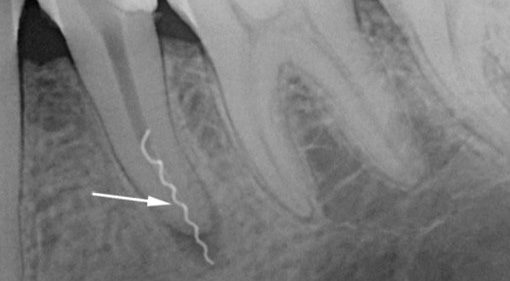

Às vezes, um médico inexperiente pode cometer erros como perfuração da raiz e interromper um instrumento no canal dentário. Como os canais nos dentes de leite são quase sempre muito amplos, a porcentagem de complicações é muito baixa, mas a gravidade é a mesma que no caso de dentes permanentes em um adulto. Como resultado da perfuração da raiz do dente e da fratura do instrumento no canal, a periodontite ou a periostite podem se desenvolver posteriormente devido à inflamação dos tecidos ao redor da raiz.

Para evitar essas complicações, o dentista pediátrico remove um chip do canal de maneira acessível e fecha as perfurações com material especial, por exemplo, ProRoot MTA. Em alguns casos, por falta de equipamentos e materiais necessários, o médico simplesmente mumifica os canais com o método resorcinol-formalina.

A foto mostra um exemplo de uma ferramenta quebrada em um canal dentário: